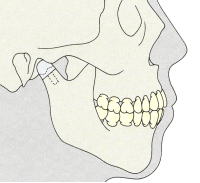

(2)関節リウマチと不正咬合

上顎前突(下顎後退症)や開咬を生じる傾向があります。

@関節リウマチと開咬

1)症状

臼歯は咬んでいるけれど、前歯は咬んでいない状態です。

2)開咬が発症するメカニズム

開咬が起こるメカニズムは、関節突起の変化が生じるからです。

3)下顎頭X線所見と開咬

リウマチのステージが進行するに従って開咬が多くなります。

(3)呼吸障害

顎関節部の破壊により次の事が生じます。

下顎骨の後退

小下顎症の側貌

上気道が狭窄し,上位頸椎の破壊などにより、睡眠時無呼吸症候群を発現(舌根と咽頭後壁との距離の短縮)